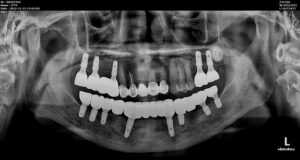

모든 치료가 마무리된

파노라마 사진과 구강 내 사진인데요.

환자분께서는

그동안 흔들리고 통증이 심한 치아로

불편감이 많으셨는데

치료 마무리 후에는

양측 저작이 편안하게 되고

심미적으로 변한 모습에 만족해하셨습니다.

처음 내원하셨을 때 보다

훨씬 자연스럽고 밝게 웃으시는 모습을 보니

저희 의료진 역시 뿌듯한 마음이었습니다.

전 > 후

이렇게 만성 치주염으로 인해 발치 후

임플란트 식립으로

무너진 교합 고경을 회복해 드린 사례를

소개해 드렸는데요.